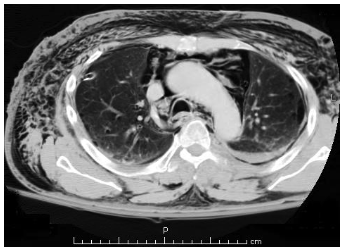

/Join us for another great week of Grand Rounds! We started out with a great discussion of the changing workforce and how the differences between generations and leadership styles impacts our interactions with our colleagues. Then we discussed the nuances of managing a dysfunctional tracheostomy with Dr. Adan. We were taken through the pathophysiology and clinical presentation of patients with pneumomediastinum and mediastinitis with Dr. Valles. Finally, Drs. Artiga, Beyde and Vaishnav gave us hands on practice with the different types of nerve blocks that can be used in the ED!